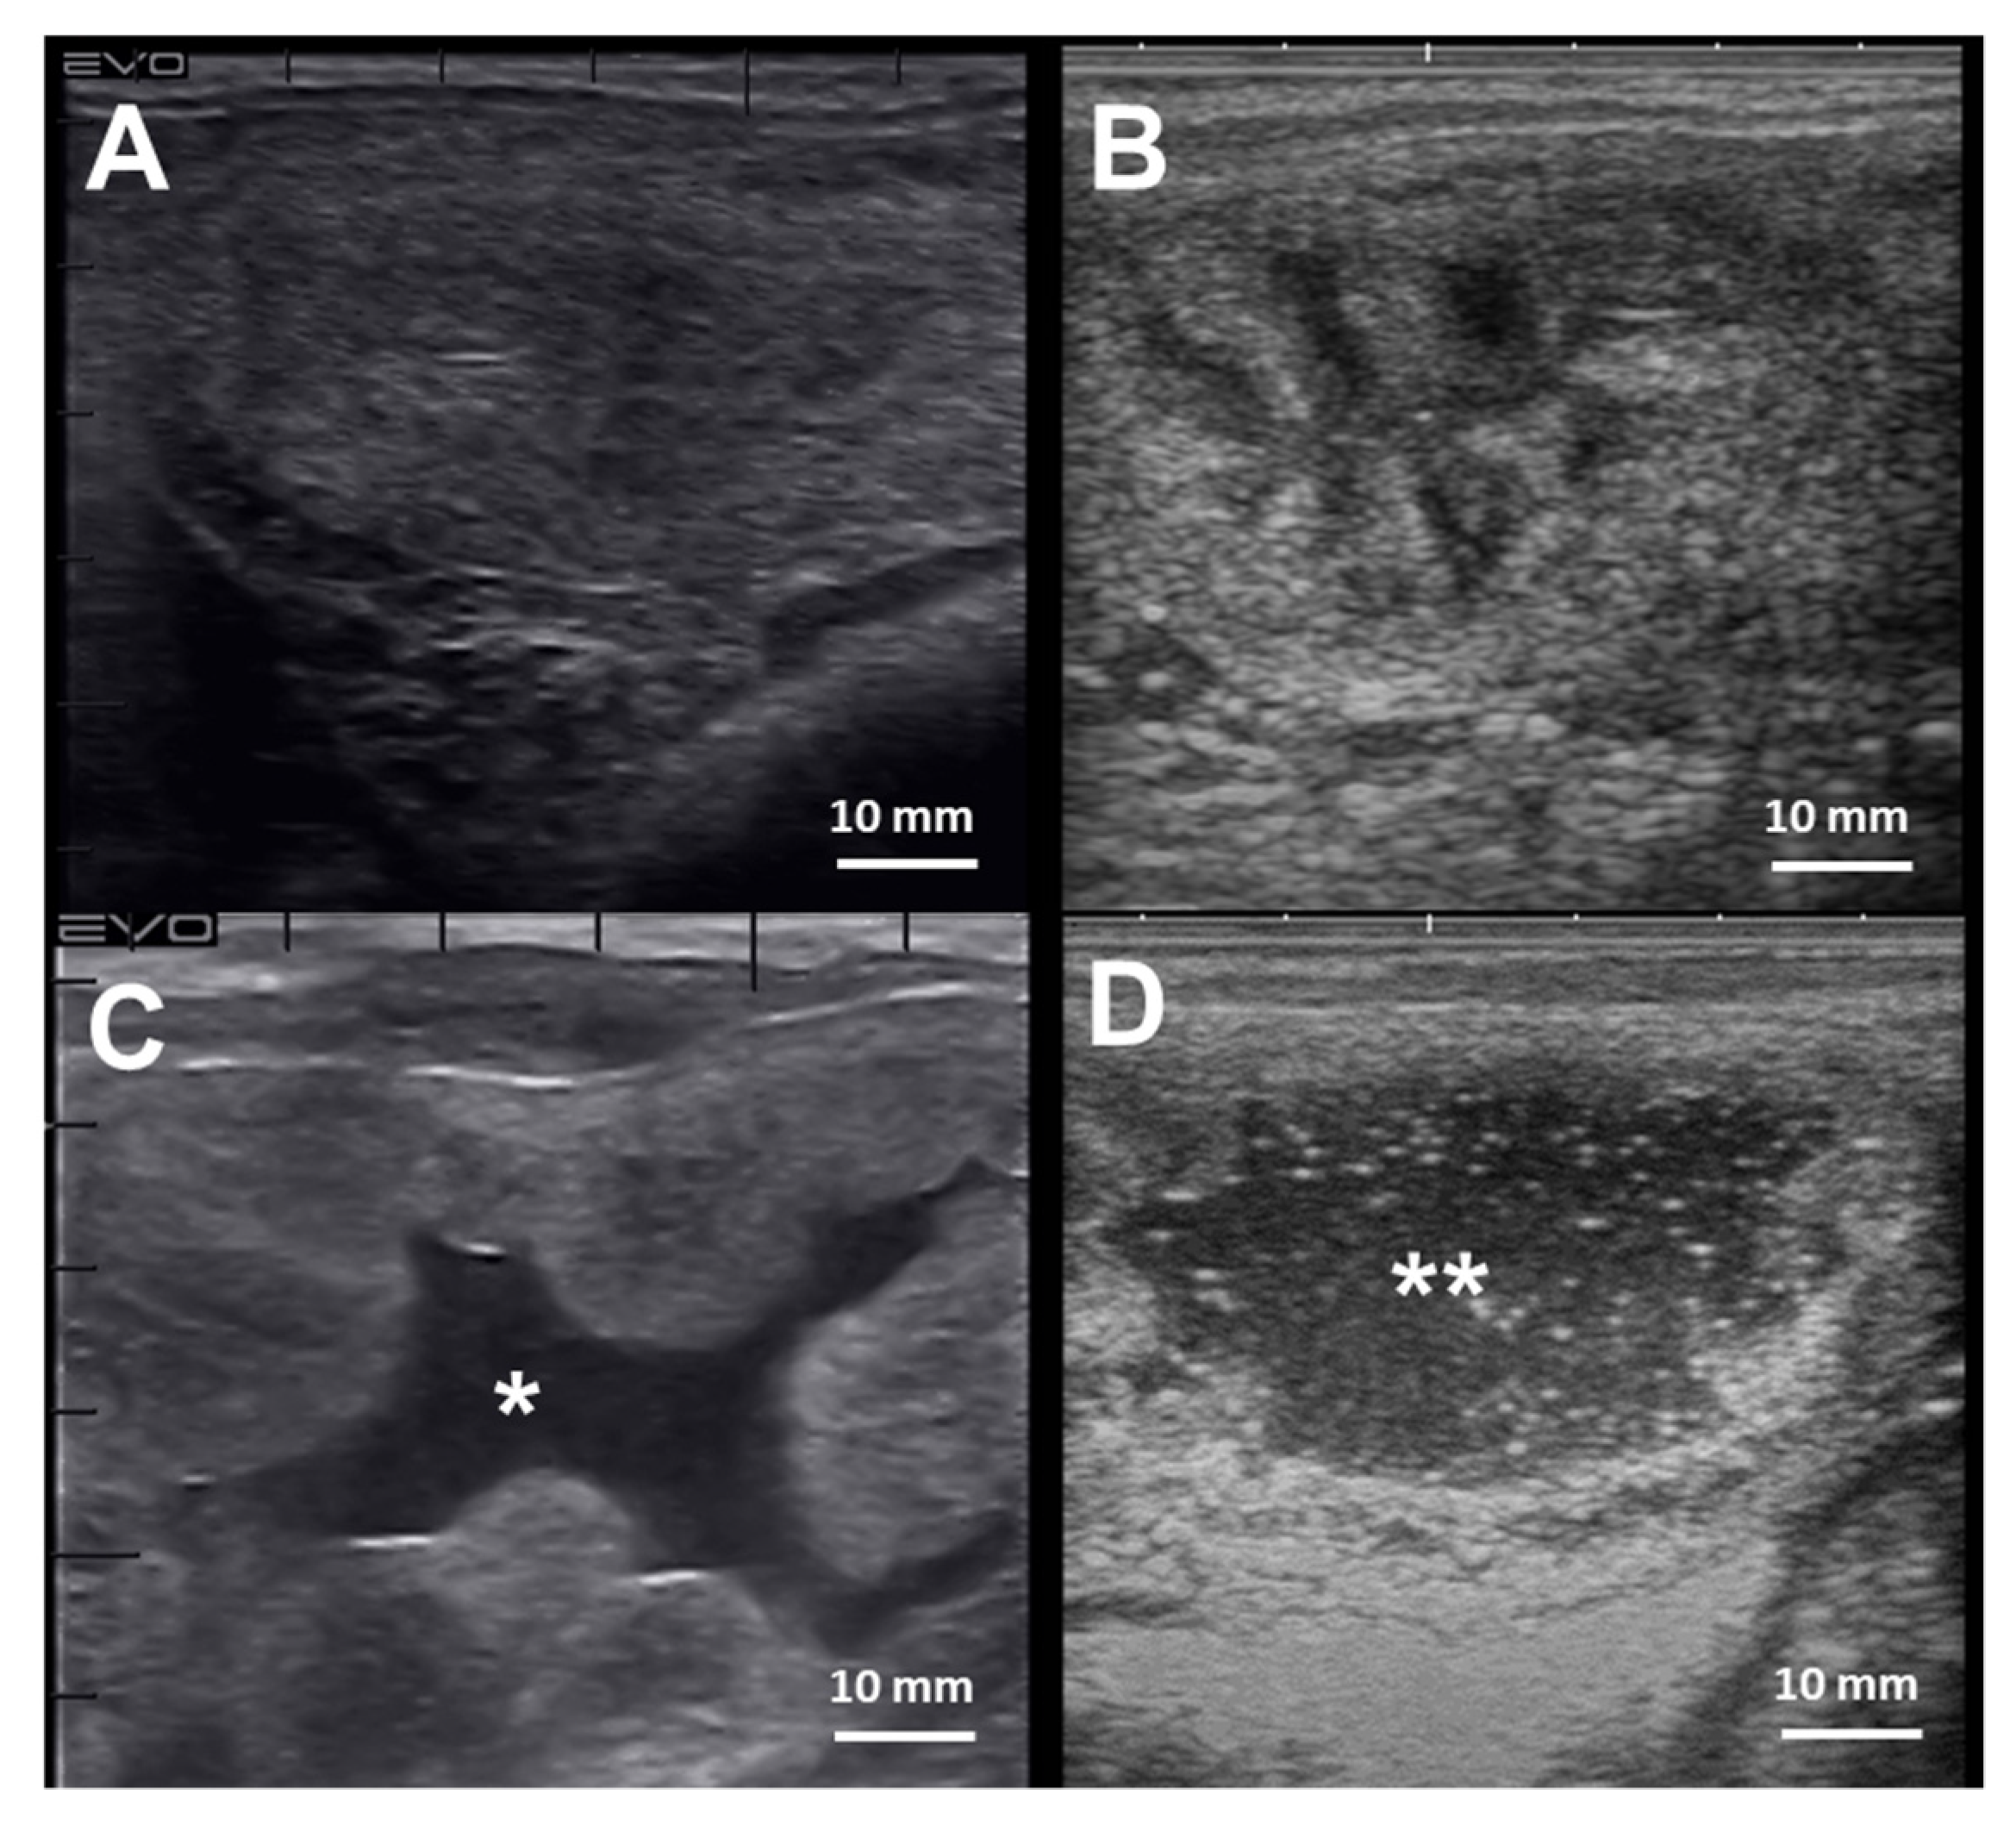

The diagnosis of endometritis entails a multi-modal approach coupled with a detailed clinical history. Endometrial culture, cytology, and biopsy are the most common tools employed to diagnose endometritis in mares [241] (Table 2). Mares susceptible to PBIE may have a history of accumulating intrauterine fluid before and after breeding (Figure 4), recurrent embryonic loss, early return to estrus, failure to become pregnant despite good breeding management, and presenting vulvar discharge.

Figure 4.

Cross-section ultrasonographic images of the uterine horns in mares: (A) An image from the equine uterus with no endometrial edema, or intraluminal fluid accumulation, typically seen in mares during diestrus; (B) the uterine horn of a mare in estrus, characterized by the presence of edema in the lymphatic vessels surrounding the endometrium submucosa giving the “orange-slice” aspect, (C) Exacerbated endometrium edema with extravasation and intraluminal fluid accumulation (*) in a mare with endometritis, and (D) extensive hyperechogenic intraluminal fluid accumulation (**) in a mare with endometritis. Scale bars 10 mm (A–D)